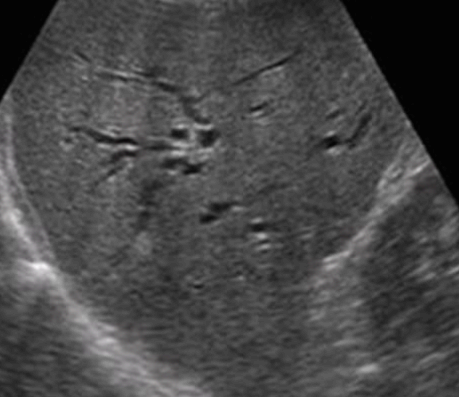

- 간내담관(intrahepatic bile duct)의 좌우직경은 2mm 이하이다. 직경이 2mm 이상이거나 portal vein 직경의 40% 이상일 때는 확장된 걸로 간주한다.

intrahepatic duct measurement (left)

intrahepatic duct measurement(right)